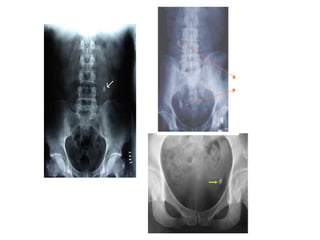

• 128.

128 Correlation of Axial,Coronal, and Sagittal MR Plate 8 Kidneys (Left Lower Pole) and Vertebral Musculature Vertebral body Quadratus lumborum Erector spinae Psoas muscle Ureter The lower poles of the kidneys lie adjacent and antero-lateral to the muscles of the back. These include the psoas, quadratus lumboratum, deep back muscles, and intermediate (erector spinae) back muscles. Notice the small hypointense circular slice of the left ureter lying on the left psoas muscle. Deep back mm.